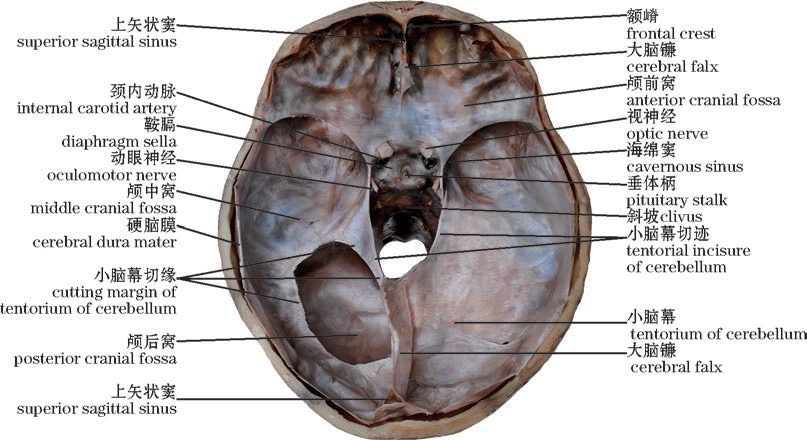

图10-45 硬脑膜(颅底内面)

The cerebral dura mater(Internal surface of the skull base)